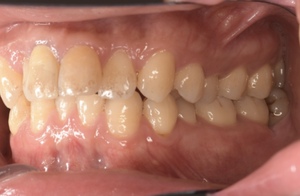

CASE 14

下顎before

下顎after

臼歯before

臼歯after

基本情報

| 年齢・性別 | 27歳・男性 |

| 主訴 | 歯石とりたい |

| 治療内容 | スケーリング |

| 治療期間 | 30分 |

| 治療費 | 約1,500円(保険診療) |

| リスク・副作用 | 知覚過敏、歯肉退縮、出血 |

| 治療方針 | 歯列不正でプラークがつきやすいため、TBIを行い定期的に歯石を除去していきます。 プラークコントロールが出来るようになったら定期検診でクリーニングを行っていきます。 |